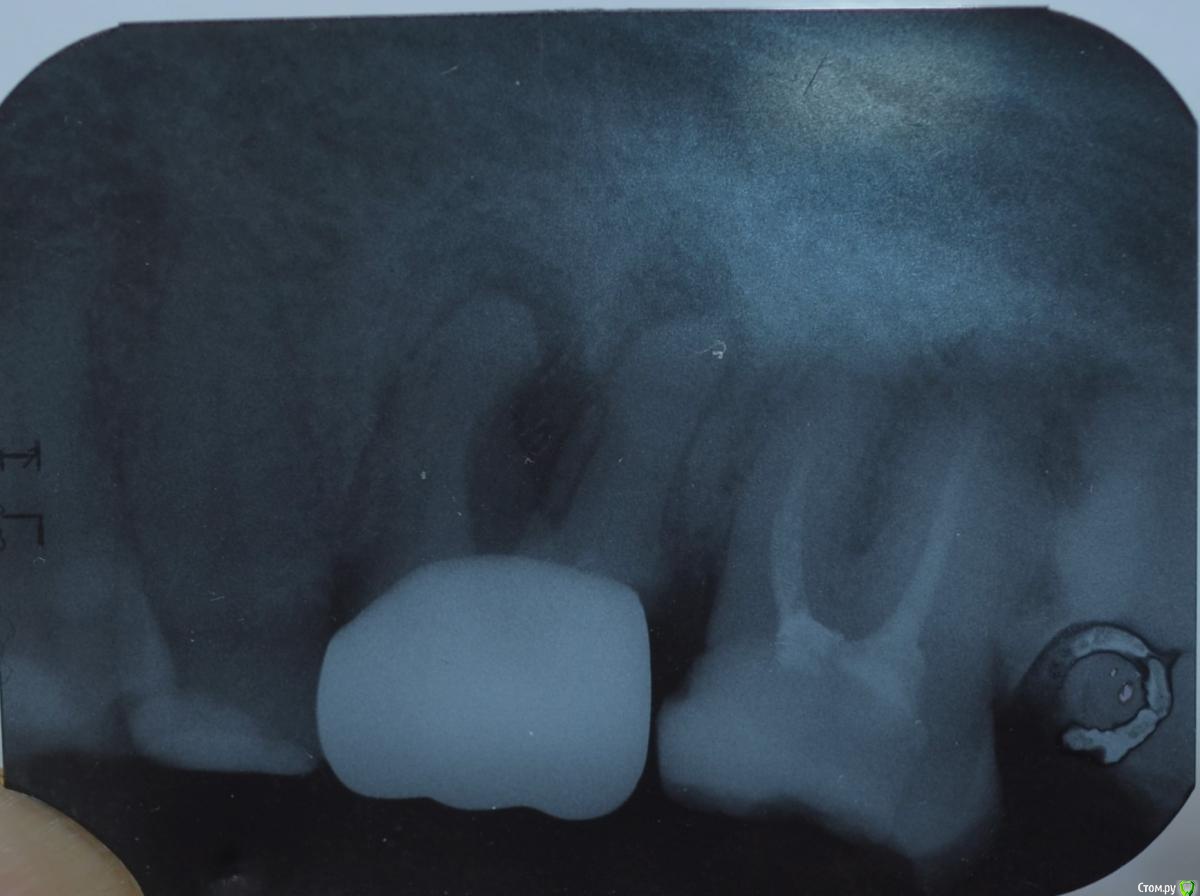

Дмитр Опубликовано 9 января, 2016 Поделиться Опубликовано 9 января, 2016 На десне под 6-ой снизу образовался гнойник. 3 января хирург сделал нарез десны, и 5 января снимок.Хочу узнать мнение специалистов: есть ли возможность спасти зуб.Кроме гнойника проблема себя никак не проявляет.Заранее благодарю за консультацию. Ссылка на комментарий

Ker Опубликовано 9 января, 2016 Поделиться Опубликовано 9 января, 2016 Удалять. Перелечивание в данном случае затруднительно, и гарантии никакой не даст.К слову, следующий зуб обязательно нужно перелечить. Ссылка на комментарий